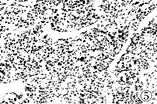

图4 平扫肝癌边界清楚

图5 术后标本免疫组化微血管染色,显示癌边缘带微血管数目稀少(×100)